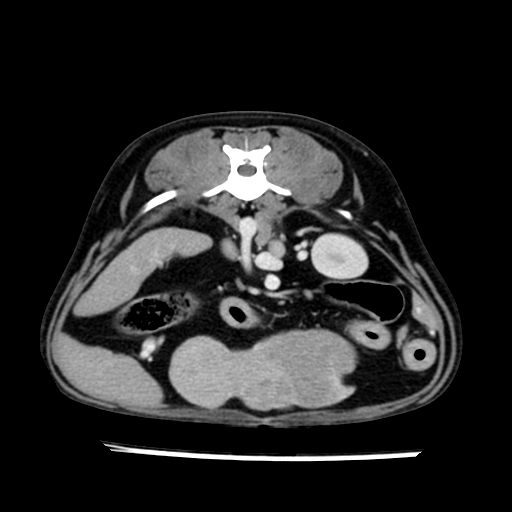

prescritto esame TAC

sequenza immagini limitata al fegato reni e surreni

le immagini ecografiche rispetto alla tac datano circa 7 mesi prima ,le surrenali sono normali nonostante il test acth sia risultato positivo .all’esame TAC dopo diversi mesi risultano aumentate armonicamente nel volume e si individua un forte sospetto di adenoma ipofisario .

sospetto adenoma ipofisario vs. meno probabilmente meningioma della base; intertiziopatia polmonare; lesione espansiva epatica, verosimilmente del lobo laterale sinistro, di sospetta natura neoplastica; lesioni spleniche di natura da definire; iperplasia/ipertrofia delle ghiandole surrenali, bilateralmente; vertebra di transizione del rachide toracico; tenosinovite cronica del muscolo bicipite brachiale di destra.

- l’esame tac e’ stato eseguito circa quattro mesi dopo la prima ecografia che non aveva messo in evidenza aumento del volume surrenalico (vedi immagini) ma solo la lesione epatica, la presenza di PU PD aveva portato ad un controllo per l’ ipercorticosurrenalismo confermato dal test act , in questo caso, si deduce che i sintomi di ipercorticosurrenalismo legati all’adenoma sono comparsi prima delle modificazioni surrenaliche, quindi in caso di sospetto ,a mio avviso e’ buona norma eseguire prima il test di stimolazione e dopo L’ECOGRAFIA per tentare una classificazione eziopatogenetica . La Tac si e’ quindi dimostrata molto valida in sensibilita’ e specificita’ riguardo la patologia surrenalica in quanto in grado di vedere o fortemente sospettare (ovviamente meno sensibile della RM) un piccolo adenoma ipofisario e le alterazioni morfovolumetriche della surrenale.